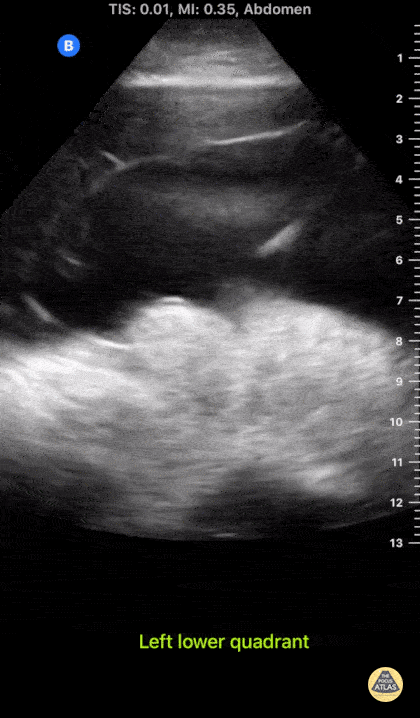

Bowel-GI - Fibrinous Ascites

A patient with cirrhosis presented with severe abdominal pain. POCUS of the abdomen revealed significant anechoic ascites. The quality of the ascites is also notable for presence of fibrinous material, increasing the pre-test probability of SBP. Paracentesis confirmed presence of >6000 WBCs; though this unique POCUS finding enabled earlier initiation of antimicrobial therapy for this patient. Parker Dixon, Hospitalist @drparkerdixon